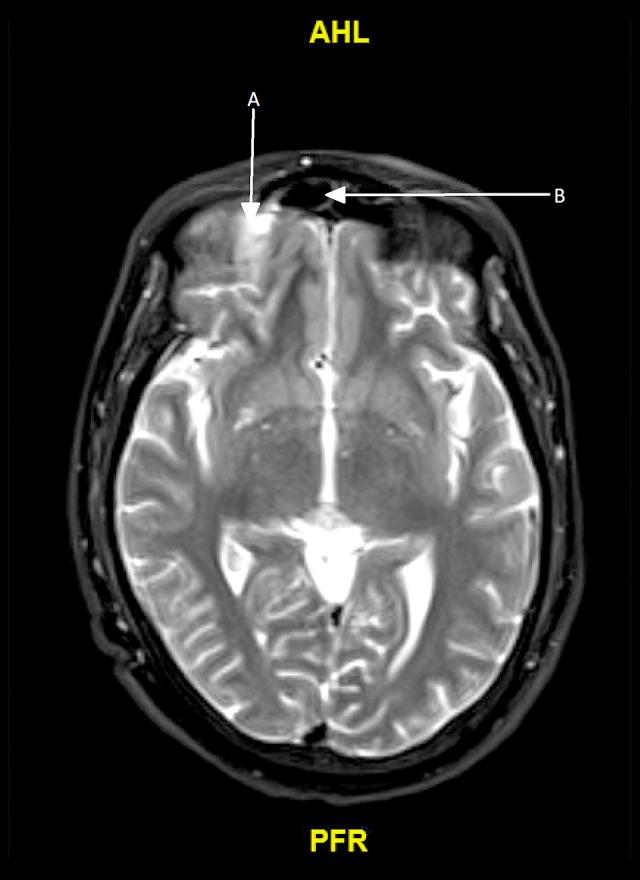

BACKGROUND We present a case of invasive sinusitis with rhinocerebral infection in a patient who had mild symptoms of COVID-19 infection and did not receive any immunosuppressive therapies. CASE REPORT A 49-year-old man with a history of uncontrolled diabetes presented to the hospital with multiple generalized tonic clonic seizures. He had recently been diagnosed with mild COVID-19 and was treated at home with supportive care only. He was found to have cerebritis in the right frontal lobe along with right fronto-ethmoid sinusitis. He underwent extensive testing with nasal endoscopy with gram stain and culture, cryptococcal studies, 1-3-Beta-D glucan, blood cultures, fungal CSF studies, Lyme disease, HIV, Fungitell assay, and galactomannan studies, which were all negative. He was started on i.v. antibacterial therapy with cefepime, vancomycin, and metronidazole along with amphotericin B. After 2 weeks, his repeat imaging revealed progression of cerebritis along with new early abscess. Given these findings, his antibiotics were changed to meropenem and the amphotericin B dose was increased. He was recommended debridement and sinus surgery but refused. During the course of treatment, he developed acute kidney injury and was switched to Posaconazole. Unfortunately, the patient decided to leave against medical advice 6 weeks into admission. He was advised to continue Posaconazole and levofloxacin but he could only afford levofloxacin. He was then recommended long-term levofloxacin. He has since recovered, with resolution of cerebritis noted in follow-up imaging 1 year later. CONCLUSIONS Our patient had mild COVID-19 infection and presented with secondary infective complications, which are usually associated with an immunocompromised state, despite receiving no immunosuppressives. It is imperative that all clinicians treating COVID-19 be watchful for fungal or bacterial co-infections in patients with active SARS-CoV-2 infection, even if the presenting symptoms are mild, particularly if other risk factors are present.

一名 49 岁男性,有未控制的糖尿病病史,因多发性全面强直阵挛发作到医院就诊。他最近被诊断为轻度 COVID-19,仅在家接受支持治疗。他被发现右额叶脑炎症伴有右额窦-筛窦炎。他接受了广泛的检查,包括鼻内镜革兰氏染色和培养、隐球菌研究、1-3-β-D 葡聚糖、血培养、真菌性 CSF 研究、莱姆病、HIV、Fungitell 检测和半乳甘露聚糖研究,结果均为阴性。他开始接受头孢吡肟、万古霉素和甲硝唑联合两性霉素 B 的静脉抗菌治疗。2 周后,他的重复影像学检查显示脑炎症进展,并出现新的早期脓肿。鉴于这些发现,他的抗生素改为美罗培南,并增加两性霉素 B 的剂量。他被建议行清创术和鼻窦手术,但被拒绝。在治疗过程中,他发生急性肾损伤,改为伏立康唑。不幸的是,患者在入院 6 周后决定出院。他被建议继续服用伏立康唑和左氧氟沙星,但他只能负担得起左氧氟沙星。然后建议他长期服用左氧氟沙星。1 年后的随访影像学检查显示脑炎症已消退,他已康复。